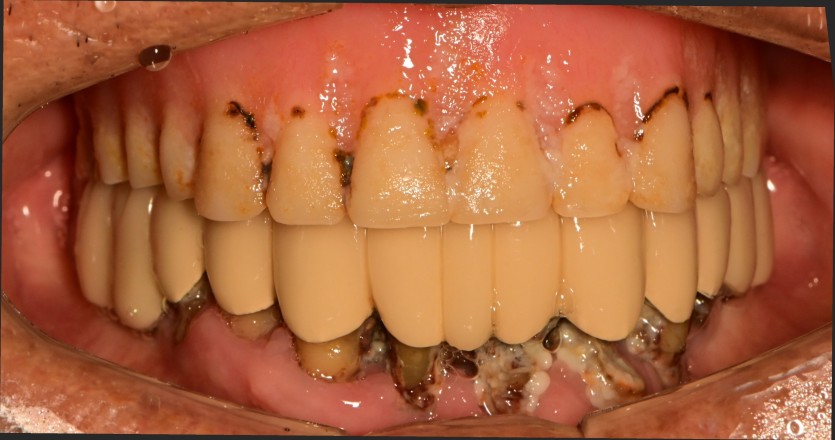

만 82세 하악 풀아치 증례

하악 풀아치 증례입니다.

(상악 기존 틀니)

6개의 임플란트로 완성하였습니다.